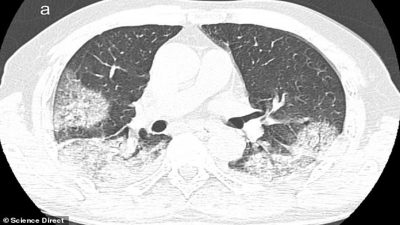

Los especialistas del Instituto Nacional de Enfermedades Infecciosas en Roma estudiaron los cuerpos de los pacientes de 65 y 67 años y detectaron, mediante rayos-X y tomografías computarizadas, un gran deterioro en la función de los pulmones.

Cuando coronavirus ataca los pulmones, provoca una inflamación en las membranas mucosas, lo genera un daño en los alvéolos pulmonares, que tienen que trabajar más para suministrar oxígeno a la sangre que circula por todo el cuerpo y eliminar el dióxido de carbono para que se pueda exhalar. La inflamación y el daño al flujo de oxígeno pueden causar que dichas áreas en los pulmones se llenen de fluido, pus y células muertas.